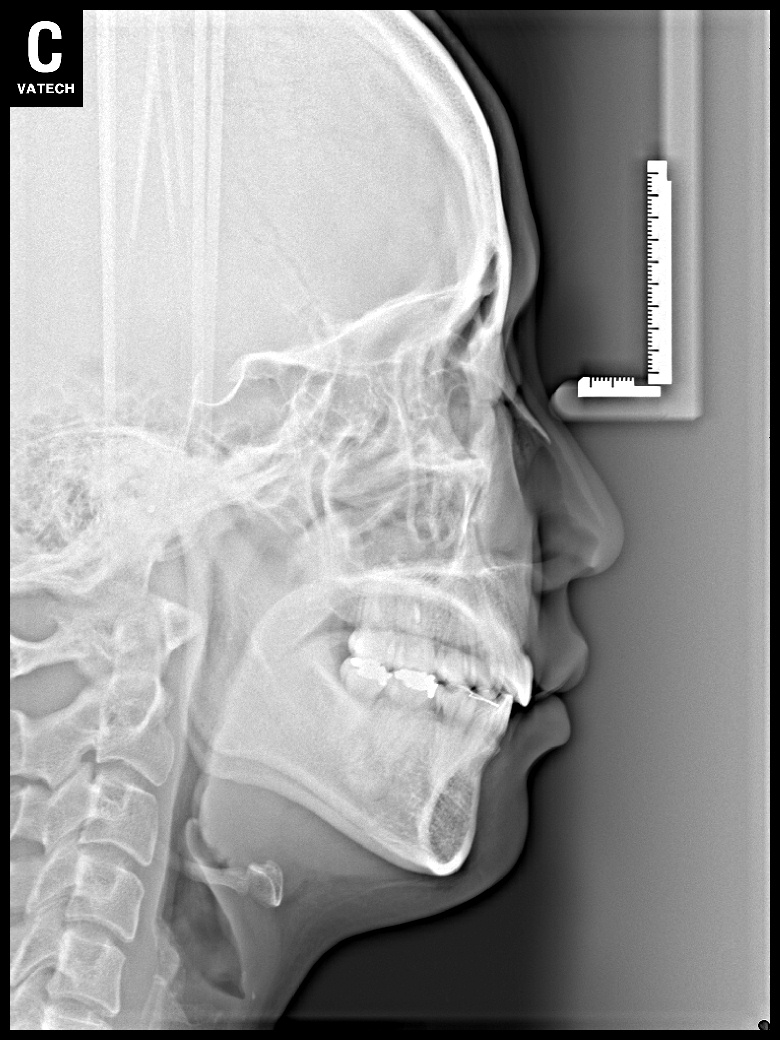

치료 전 사진입니다.